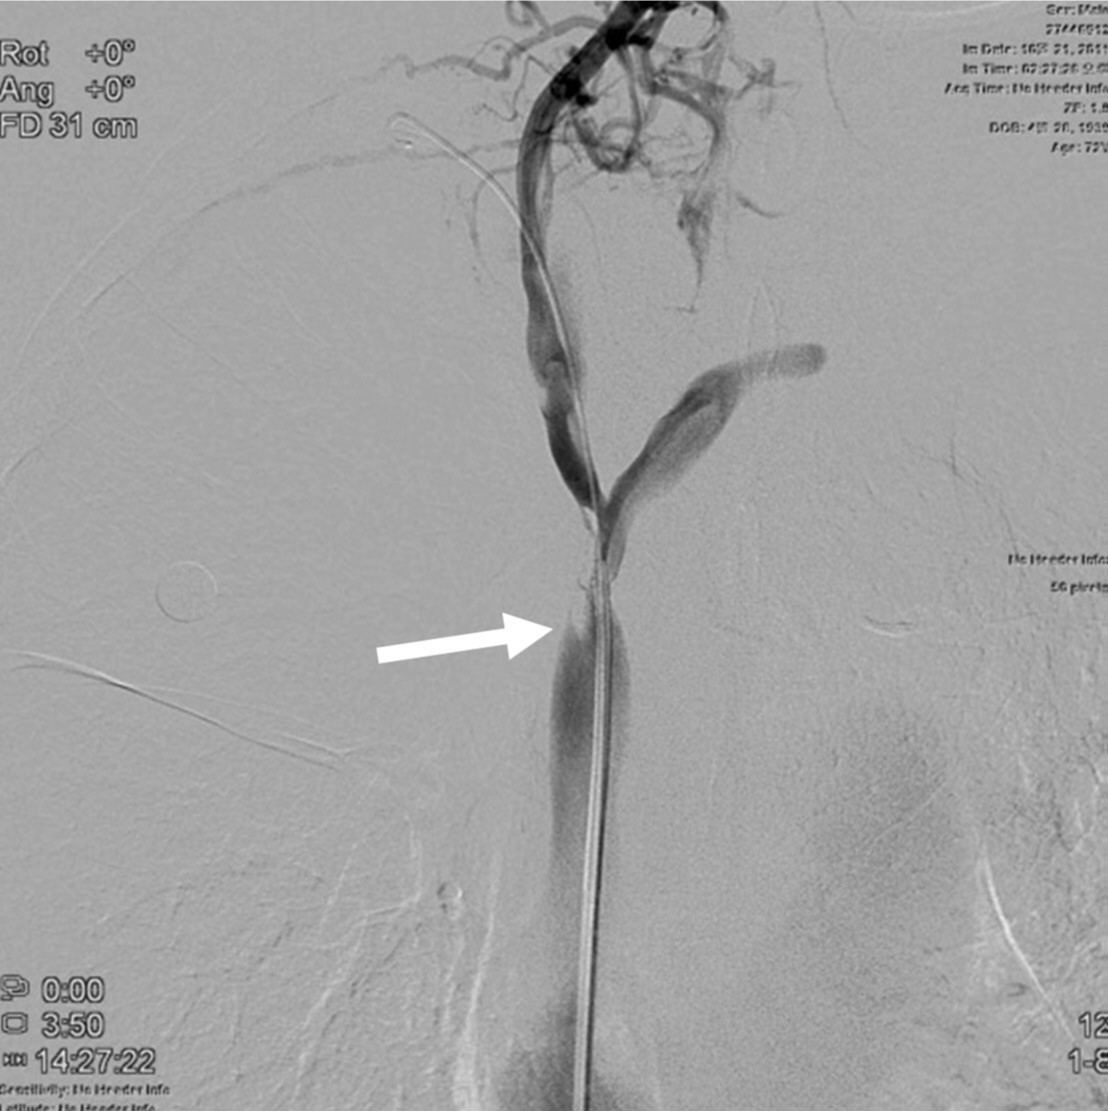

Fig. 2.

Fig. 2. On right brachiocephalic venogram, the distal end(arrow) of the stenosis is only seen with no visualization of its proximal end.